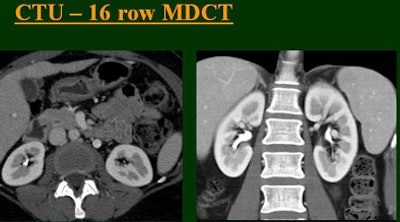

At the 2004 RSNA meeting in Chicago, Dr. Vassilios Raptopoulos from Massachusetts General Hospital and Harvard Medical School in Boston evaluated single-, four-, eight-, and 16-row detector scanners in 200 patients using a single-acquisition biphasic CT urography (CTU) protocol. As the number of detector rows increased, visualization -- especially of the calyces -- improved significantly.

"As we've been scanning through the kidneys, we've been noticing that there has been an increase in the quality images as we go from (single-) to four-, eight-, and 16-row detector scans," Raptopoulos said. "Our purpose, then, was to assess the quality of CTU with progressively improving CT technology from (single-) to 4-, 8-, and 16-row scanners, using a split-injection single scanning technique."

| Top to bottom: Split-bolus CTU improves significantly using a nearly identical protocol but with the addition of more detector rows, from single- (spiral), four-, eight-, and 16-row scanners. All images courtesy of Dr. Vassilios Raptopoulos. |

The single-row scanner required two breath-holds; the other scanners reduced scan time from about 20 seconds (four-slice) down to seven seconds (16-slice). Collimation for the single-row scanner was 5 mm, with 3-mm overlapping reconstructions. Collimation for the four-, eight-, and 16-row scanners was 2.5 mm, 1.5 mm, and 0.5 mm, respectively, with the patients scanned in a prone position.

Based on multiplanar reformatted (MPR) images, there was significant upscale improvement in calyceal detail from the isotropic images provided by single-detector scanning (median score 2) to four- (median score 3), eight- (median score 4), and 16-detector scanning, Raptopoulos said. On MPR images the calyceal were 1, 2, 3, and 5, respectively. The median ureteral filling was 4 for the upper and left-lower ureters, and 3 for the right-lower ureters.

"We're using this technique of biphasic injections not only in CTU, but in general abdominal scanning in trauma, in renal CT, and we can see the renal vessels quite well in relation to the collecting systems," Raptopoulos said. "Combined excretory- and parenchymal-phase CTU is a practical technique, allowing a decrease in patient scanning," he said. "Sixteen-row CTU with the patient in a prone position significantly improves the quality of the exam."